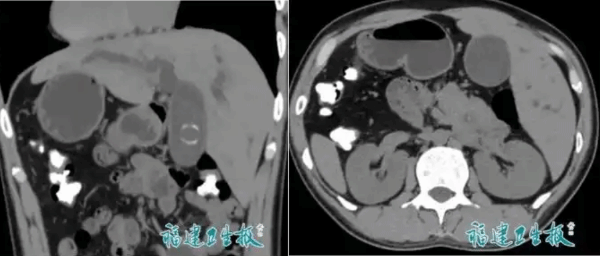

一名男子因腹痛剧烈、皮肤泛黄到医院看病。检查结果令医生们十分意外:这名男子除了患有胆总管结石外,还有一个特别的情况——他的心脏长在右边,而且内脏完全反位,通俗地说就是“五脏六腑像照镜子一样颠倒了位置”。

据了解,“镜面人”是一种极为罕见的病例,其发生率仅为百万分之一。针对这一特殊状况,医疗团队第一时间转变思路,把所有解剖学知识“反向运用”,并细致地规划手术方案。

经过两个小时紧张且精细的“镜像手术”,医生们精准取出了结石。整个手术过程十分顺利,用时仅两小时,出血量不足50ml,堪称“教科书级”的精准操作。术后一周,该男子便康复出院,恢复状况良好。